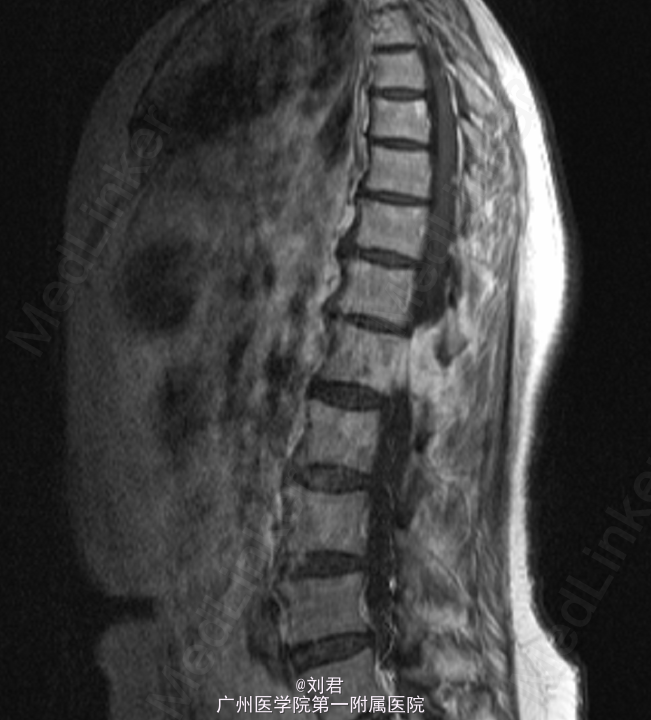

患者,女,52岁,因“右后髂部疼痛1年余。”入院。 患者1年余前出现右后髂部疼痛,疼痛程度较轻,不伴有下肢放射痛、下肢活动受限等不适.

脊椎外观无畸形。胸腰椎无明显压痛、叩击痛。双下肢直腿抬高试验阴性,双下肢感觉无异常,肌力、肌张力正常。腰椎椎间盘扫描:腰1椎体肿瘤,考虑椎体血管瘤可能。建议增强MRI扫描观察。腰椎磁共振增强扫描:腰1、2肿瘤,倾向于恶性肿瘤,转移?骨髓瘤?

初步诊断:腰椎肿瘤. 手术指征明确,行腹主动脉造影+腰椎动脉超选造影+胸12、腰1、2动脉栓塞术,后行腰椎肿瘤后路肿瘤切除、椎管减压、内固定术。

术后病理:(腰1椎体)血管瘤。术后予抗感染、止痛等治疗。患者术后恢复可,复查腰椎X片示内固定位置可.